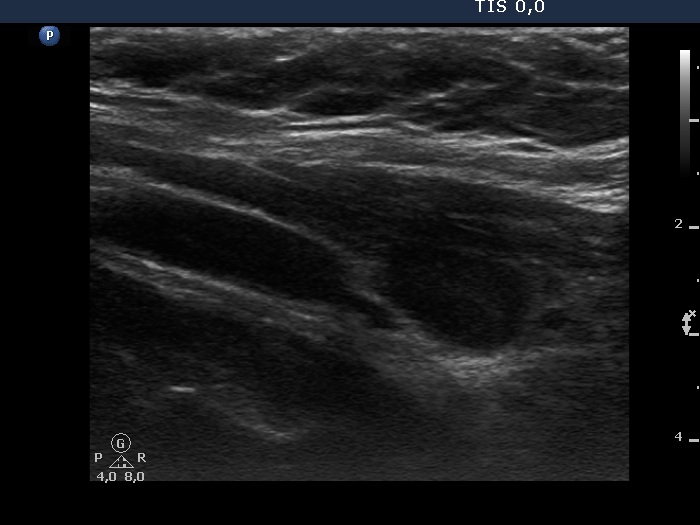

Consecutive patients with the final diagnosis of Hashimoto's thyroiditis - case 6 (254) (ultrasonographic picture 6)

Left lobe, another longitudnal scan.